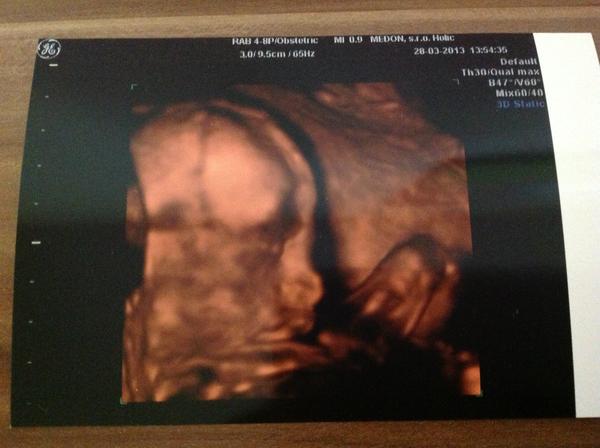

Ahojte kocky mi sa tiez pridavame termin mame 12 augusta. Pretrpeli sme si stresy pretoze nam vysiel vysledok z krvi 1:7 DS isla som na amnio kde nam koli takemu vysokemu skore dali vysledky do 3 dni na 5 najcastejsich chromozomov zatial je vsetko v poriadku ostatne chromozomy vysetria do konca buduceho tyzdna. Co vam budem hovorit darmo Vam povie niekto nestresuj sa ked ide babo.